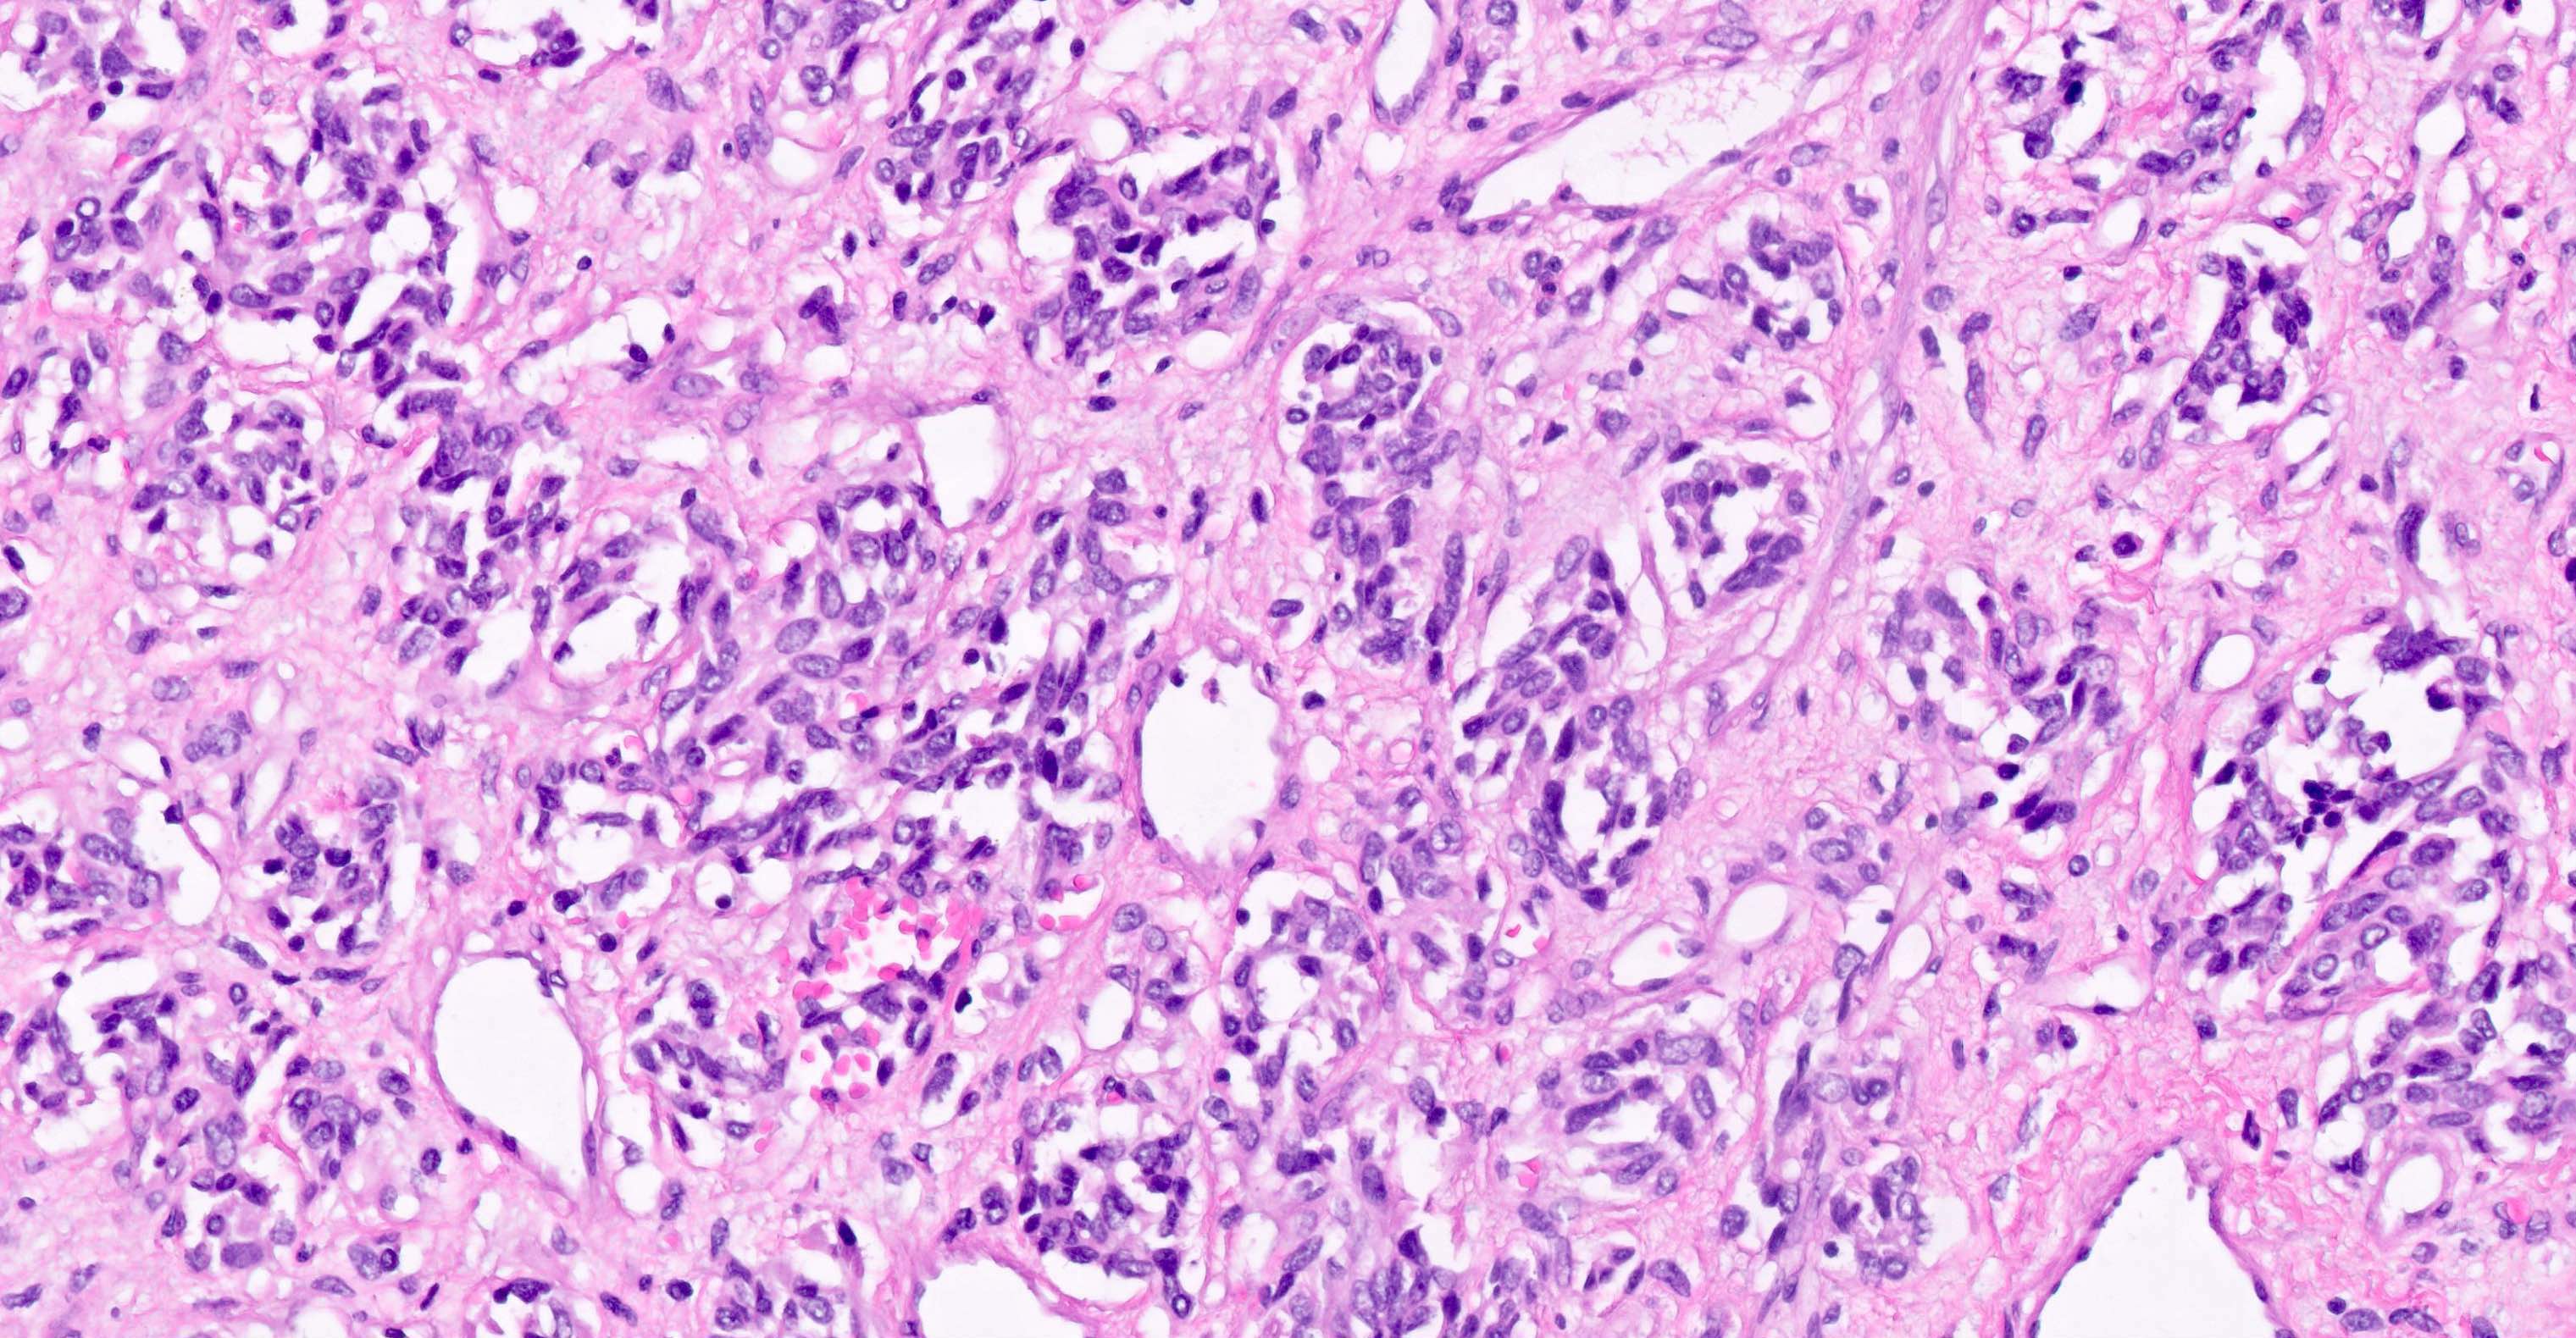

Microscopic (histologic) images

- Solitary fibrous tumor (98 - 100%), regardless of morphology or site, typically strong and diffuse (Pathology 2014;46:389, Pediatr Dev Pathol 2018;21:389, Acta Neuropathol 2013;125:651)